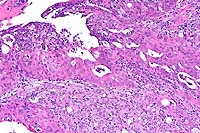

- 1. Heart and skeletal muscle: Degeneration, vacuolar, severe.

- 2. Heart and skeletal muscle: Regeneration, moderate.

Etiology: Abnormal storage of glycogen in cardiac myocytes

and skeletal muscle. Condition: Glycogen Storage Disease Type

II.

- The periodic acid-Schiff (PAS) reaction shows that many vacuoles

are PAS positive and diastase sensitive (longer diastase digestion

times may have to be used). No evidence of heart failure has

been seen as yet. Mice will be used as models for gene therapy.

40x

obj

- Case 15-1. Heart. Moderate numbers of cardiac myocytes

contain large vacuoles.

- Case 15-1. Skeletal muscle. Muscle fibers have cytoplasmic

vacuolation.